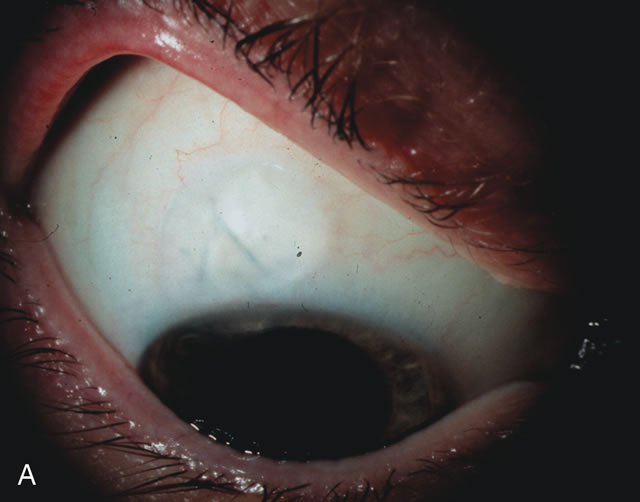

Fig. 3. Partial bleb failure following clear corneal phacoemulsification with foldable IOL. A. Preoperative bleb appearance prior to temporal lens extraction. Preoperative IOP was 12 mm Hg on no antiglaucoma medications. Time from 5-FU trabeculectomy surgery to lens extraction was one year. B. Bleb appearance 2 months after clear corneal cataract surgery with topical anesthesia. Following lens extraction, increased vascularity was noted along with decreased size of the filtering bleb. IOP increased to 20 mm Hg as early as 2 weeks after surgery, necessitating topical antiglaucoma therapy. C. High magnification view of bleb before lens extraction demonstrates diffuse pale bleb. D. High magnification view of bleb 2 months after surgery. There are vessels surrounding the nasal side of the bleb and the overall bleb size is smaller.